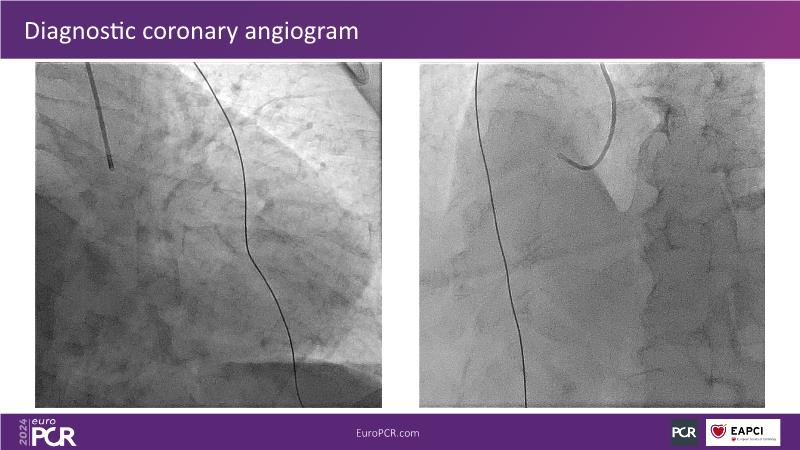

Tune into this 2024 session for insights into the latest ESC guidelines, strategies to prevent and treat no reflow, and an examination of trials like TASTE, TAPAS, and TOTAL on coronary thrombus management. Explore also the outcomes of the CHEETAH study, pondering a potential paradigm shift, and delve into a case study on thrombus removal in a patient with high thrombus burden.